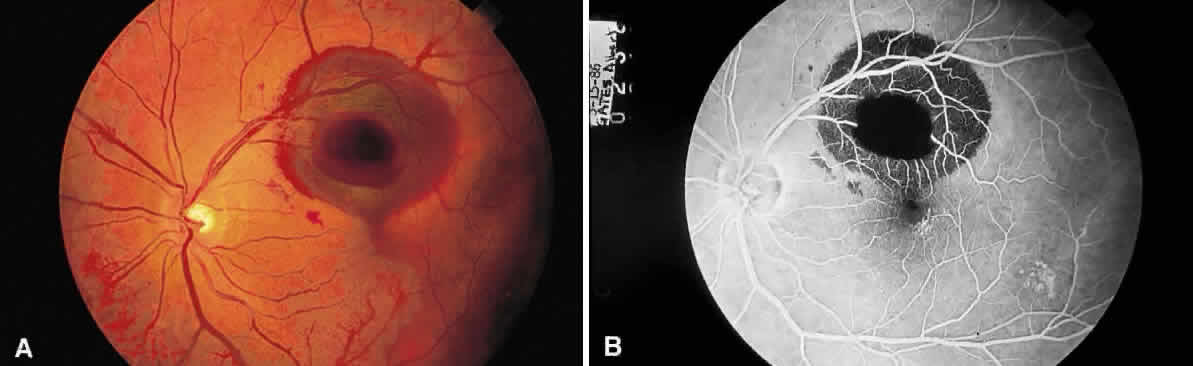

The pink color of the normal optic nerve head is reflective of the vascular supply to the surface of the disc. Loss of the vascularity or replacement of the neural tissue by opaque glial tissue alters the color of the disc (Fig. 7). Anatomical variations in the retina alter the appearance of lesions, in particular, the macula and the retinal periphery. The macular cytoarchitecture differs in that the ganglion cell layer and nerve fiber layers are displaced centrifugally from the fovea. Therefore, on ophthalmoscopic examination, conditions that affect these layers are not apparent in the fovea. Tay-Sachs disease involves the accumulation of storage material by ganglion cells. Since these cells are not present in the fovea and the presence of the storage material opacifies the normally transparent retinal tissue, the retina surrounding the fovea is opacified, but the fovea transmits the normal choroidal color (red), accounting for the presence of the “cherry-red spot” in this condition. Notice that the opacification (white appearance) of the perifoveal retina is not seen beyond the macula. The reduced concentration of ganglion cells in the extramacular retina explains the focal nature of this retinal opacification (Fig. 8). The oblique orientation of the outer plexiform layer (connection of rods and cones to the bipolar layer) in the macula explains the appearance of several lesions. Cyst-like spaces may occur at the level of the outer plexiform layer of the macula (Henle's layer) as the result of the accumulation of fluid or the hydropic swelling of Müller cells with subsequent disruption and the formation of the spaces.1,2 These cyst-like spaces (they are not lined by an epithelium and are therefore not designated as true cysts) are oriented along the plane of Henle's layer and appear to originate from a central zone (Fig. 9), like the petals of a flower. The fluorescein angiographic appearance of cystoid macular edema is frequently described as having a petaloid pattern3 (Fig. 10).

Fig. 10. Fluorescein angiographic appearance of cystoid macular edema described as having a “petaloid pattern.”